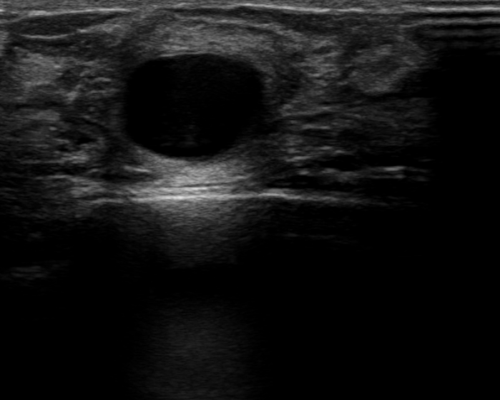

For segmentation, we employ the zero-shot method MedCLIP-SAMv2 [koleilat2024medclip, koleilat2024medclipsamv2]. It works by computing activation maps from a pre-trained CLIP model, and using them as query for the Segment Anything Model (SAM) [kirillov2023segment]. Activation maps are computed using Multi-Modal Information Bottleneck Attribution (M2IB) [wang2023visual], using a target image and a query prompt. Here, we aim at improving the quality of the activation maps on different concepts by leveraging KT. This, in turn, should result in a higher accuracy of the final segmentation. We target four different segmentation tasks: lung nodules segmentation on CT images (UnitoChest), pneumothorax segmentation on CXR images (SIIM Pneumothorax), breast nodule segmentation on ultrasound images (UDIAT), and glioma segmentation in MRIs (BraTS23).

The overall results across all segmentation tasks are presented in Tab. 7. The captions used for inversion are reported in the supplementary material. To compute the M2IB activation maps on the fine-tuned models, we employ descriptive prompts as suggested in [koleilat2024medclipsamv2]. The prompts are reported in Tab. 7 as P1 to P4 for each task. We also report reference results of MedCLIP-SAMv2 on each task. Compared to the original setting of MedCLIP-SAMv2, lung nodules and lung pneumothorax are completely novel concepts. There is also a slight difference in the brain glioma class compared to the original brain tumor task, explained in the supplementary file. We employ three metrics to assess the segmentation quality, namely the Dice-Sørensen Coefficient (DSC), Normalized Surface Distance (NSD), and Intersection over Union (IoU). We report results with different values of fine-tuning learning rate. We can observe an increase in segmentation metrics across all tasks, notably in breast ultrasound (NSD 59.44% to 61.56%) and brain MRIs (NSD 20.97% to 22.26%). For lung nodules and pneumothorax, the improvement is less pronounced, probably because the novelty of the task makes improving more difficult in the MedCLIP-SAM setting. We report some visual examples on breast tumor segmentation in Fig. 5, showcasing the improvements of KT.

Results of knowledge transfer on MedCLIP-SAMv2 with different values of learning rate are shown in Tab. 14. We report illustrative examples of the improvements achieved by knowledge transfer in Fig. 11 and Fig. 12. The captions used for inversion for segmentation can be found in Tab. LABEL:tab:captions-segmentation.